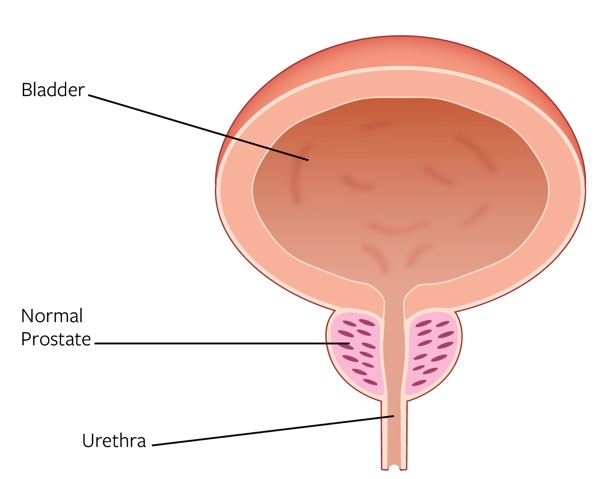

BPH Disease Overview and Diagnosis

BPH refers to the non-malignant enlargement of the prostate gland. As the prostate enlarges, the gland presses against the urethra, which may obstruct or restrict the flow of urine from the bladder and result in uncomfortable LUTS, such as urgency, frequency, urinary retention, straining to urinate and a weak urinary stream. Without treatment, prolonged obstruction may eventually lead to acute urinary retention, urinary tract infections or renal insufficiency. An enlarged prostate can range between roughly 30 ml to above 300 ml. As prostates increase in size so does the complexity of shape where the obstructive tissue will grow back into the bladder (called an intravesical component).

Normal Prostate versus Enlarged Prostate

While some BPH patients are asymptomatic, most will experience symptoms, which generally become more bothersome with age. According to the AUA guidelines, it is estimated that 90% of men between the ages of 45 and 80 will experience LUTS, and 50% of them will experience moderate-to-severe symptoms by the time they are 85 years old, which we believe are predominantly caused by BPH. Furthermore, 50% of men between the ages of 51-60 have pathological BPH. Symptoms associated with BPH can have a significant impact on a patient’s quality of life, including inability to sleep through the night, limiting activities due to proximity to the bathroom, impact on relationships, professional life and social activities, ongoing embarrassment and frustration and impact on sexual function. According to our internal marketing survey, 99% of men diagnosed with BPH say symptoms impact their quality of life.